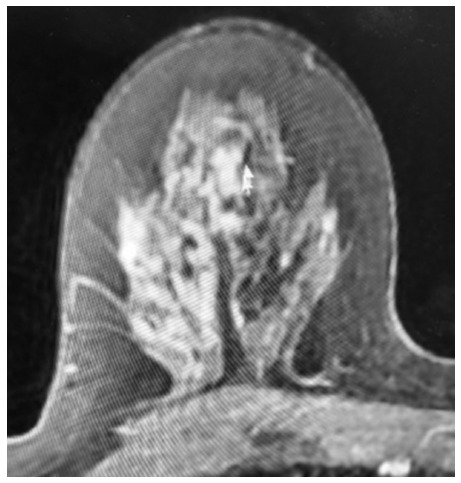

Ductal Carcinoma In Situ: Non-Mass Enhancement on MRI 10 Years Before Mammographic Microcalcifications.

In developed countries, the lifetime risk of developing breast cancer among women is 11%. Therefore, screening asymptomatic women for breast cancer is widely accepted as preventive health care. Mammography is the primary imaging modality for the detection of breast abnormalities. Digital breast imaging detects 90% of symptomatic or asymptomatic cancers. The sensitivity, specificity, and negative predictive values of this modality are each about 90%. As a standard of care, the Breast Imaging Reporting and Data System (BI-RADS) is used to quantify increasing degrees of positive predictive values in mammography. This can help clinicians identify abnormalities that may need additional imaging studies or biopsies. To reduce false-negative breast cancer screening results, efforts have focused on increasing the sensitivity of mammography or supplementing it with ultrasound or MRI. Advanced practitioners are strategically positioned to detect incongruities between imaging techniques and physical assessments. With increased knowledge, advanced practitioners are better prepared for shared decision-making discussions regarding follow-up imaging procedures. The case report in this article describes a 10-year discordance of imaging that proved to be high-grade ductal carcinoma in situ (DCIS) and offers a hypothesis of the physiology to explain this discordance. A better understanding of breast imaging will enable the advanced practitioner to recommend the most appropriate follow-up study for patients.